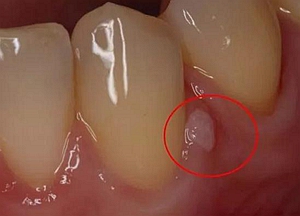

所以根管治療清理干凈殘髓至關(guān)重要,還有牙膠尖一定要完整填充根管,不能出半點差錯,否則牙齦上的膿包會越變越大,及時排膿消炎減少瘺管感染,牙齦也可以慢慢恢復(fù)正常